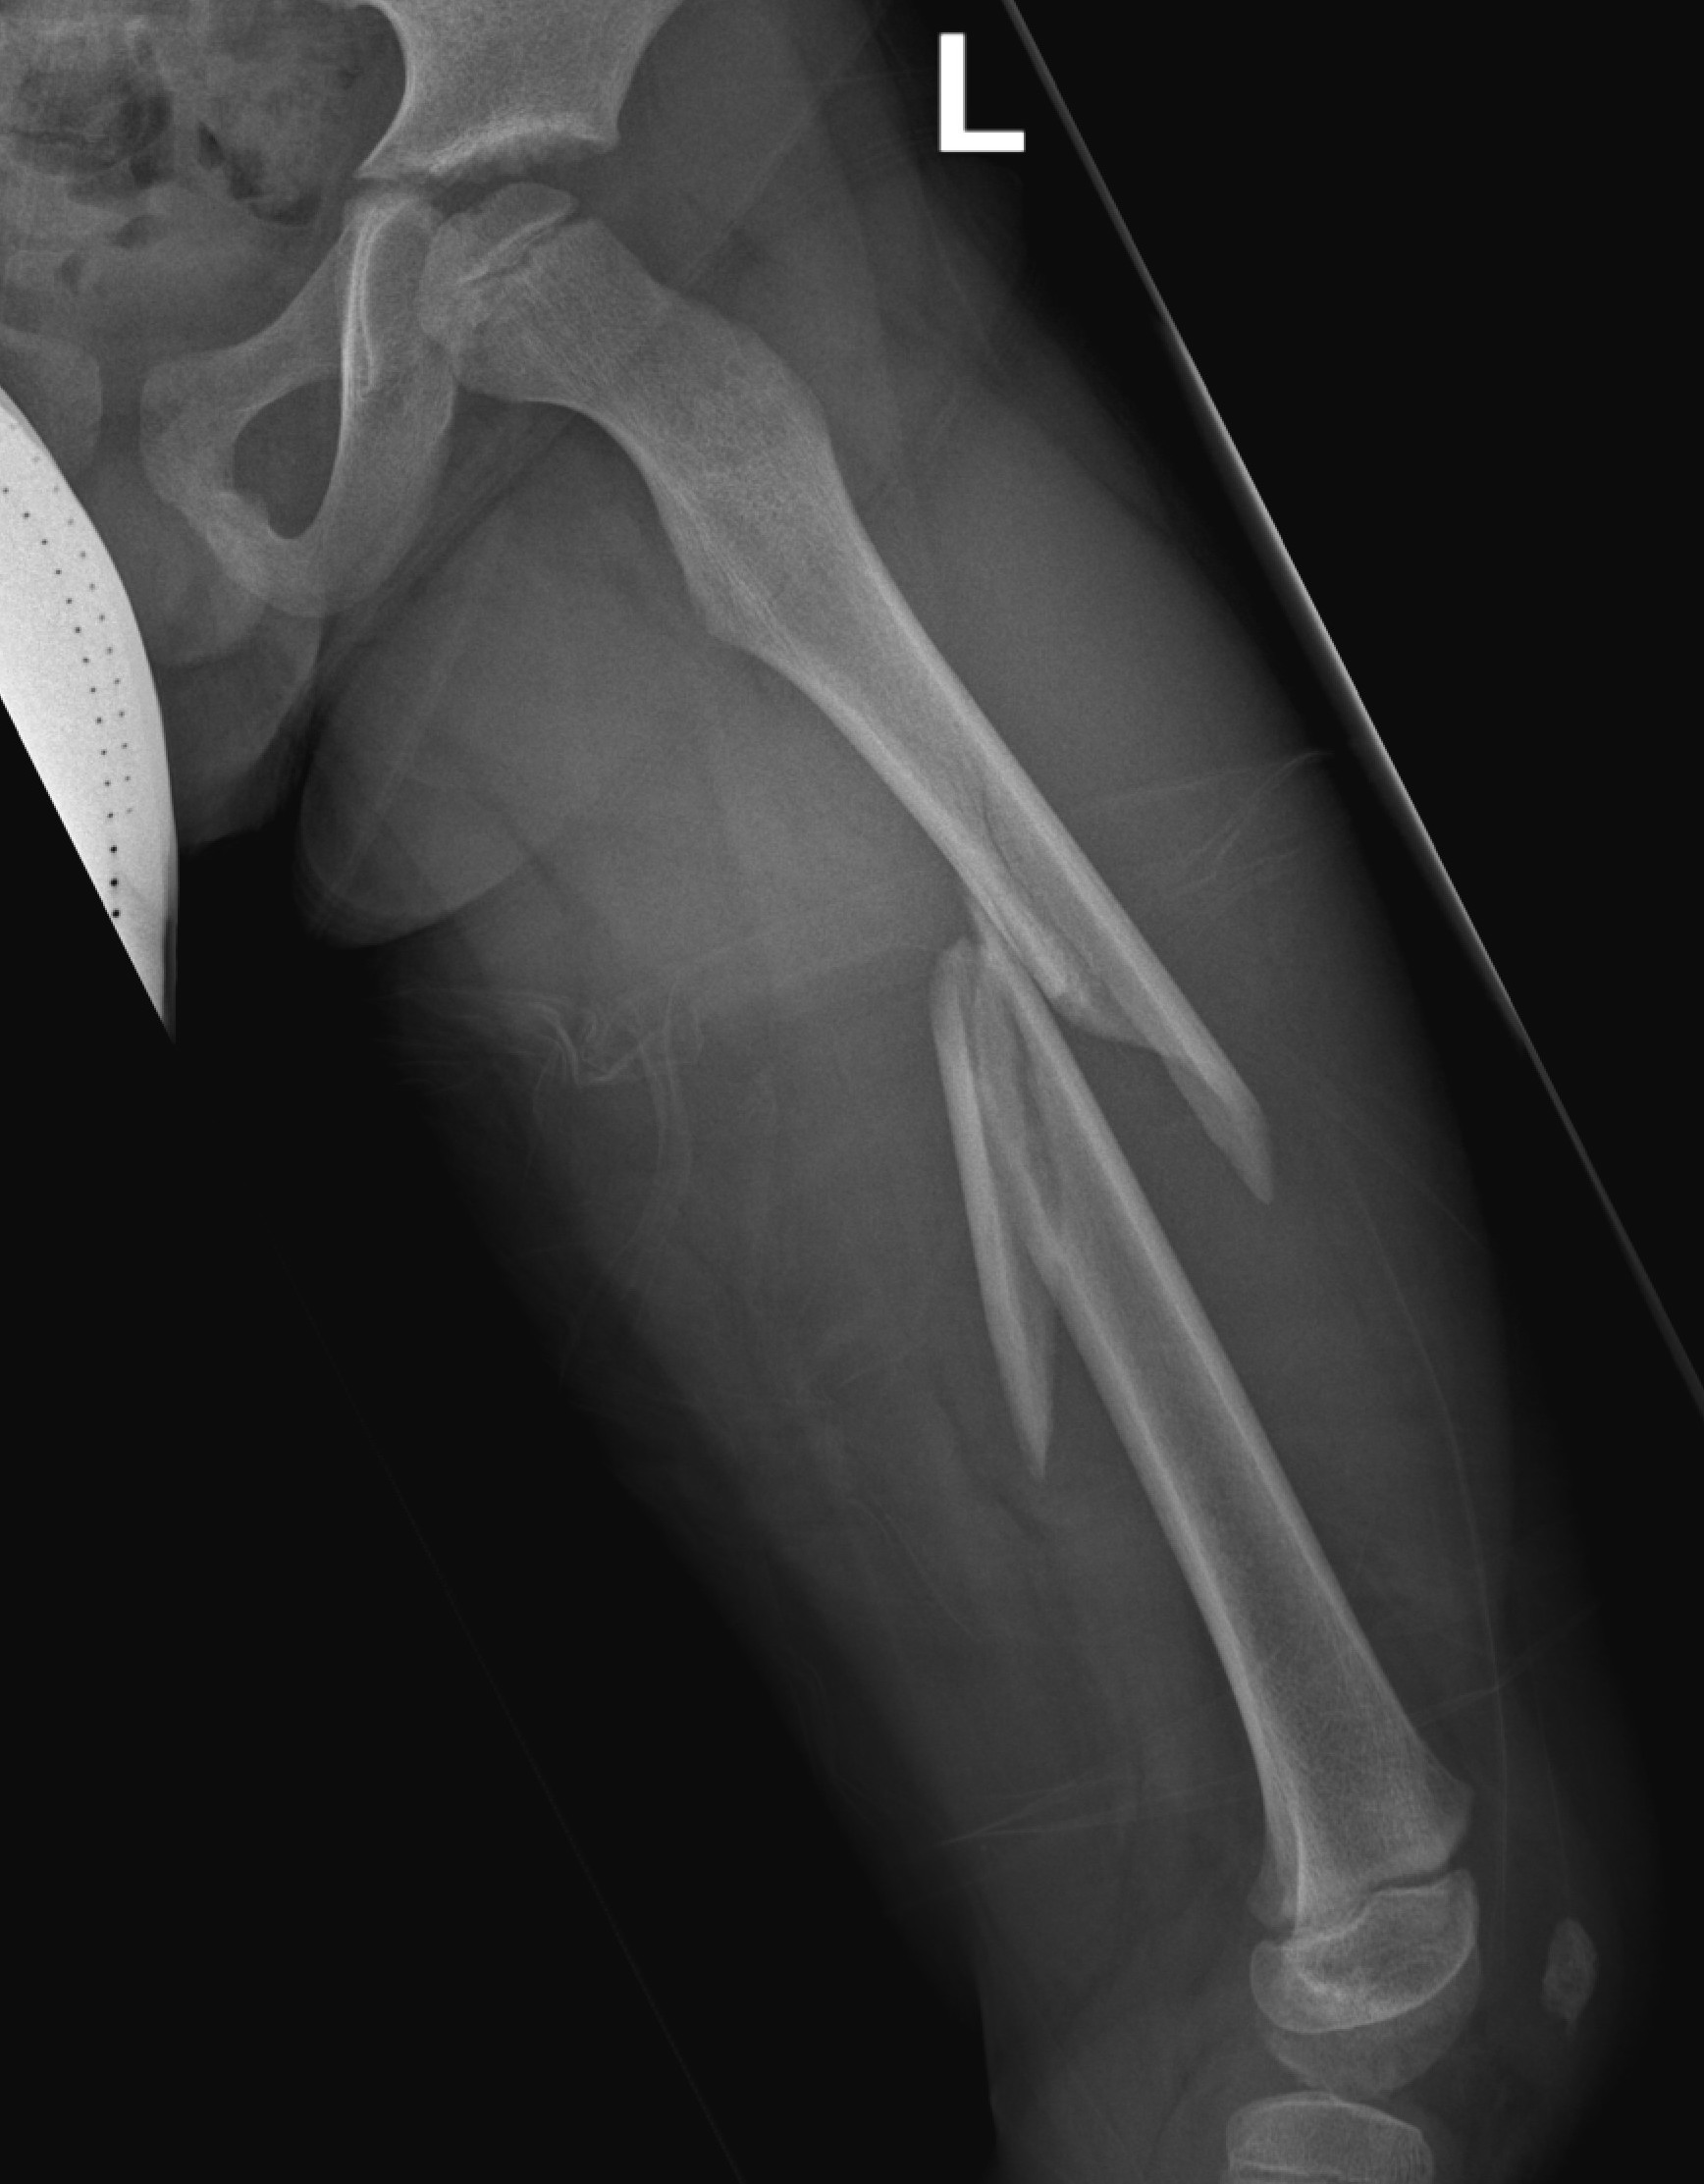

Femur plates

Indication

- length unstable fractures (spiral / comminuted)

- distal or proximal fractures

Options

Open plating

Submuscular bridge plating

Technique

- supine on radiolucent table or traction table

- proximal and distal incisions

- blunt dissection to periosteal layer

- run bristow or cobb elevator submuscularly

- 3.5 or 4.5mm LCP plate submuscularly

- indirect reduction techniques

- if inadequate reduction need to open